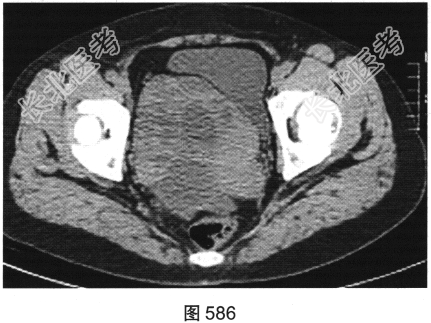

患者女性,38岁,因“间断性下腹部疼痛1周”入院。既往:否认肝炎、结核病史。查体:下腹部压痛。患者行腹部CT检查,见图582~图589。

- 多项选择题2.[提示]患者盆腔CT表现见图590、图591。根据以上两幅盆腔CT图像,可以看到哪些阳性表现( )

A、直肠乙状结肠交界区肠管壁厚,强化不均匀

B、双侧髂血管周围多发结节影,可见强化

C、右侧附件区较大囊实性占位性病变,可见不均匀强化

D、右侧附件区多房囊性占位性病变,未见强化

E、盆底腹膜多发结节状软组织影,可见强化

F、盆腔大量积液